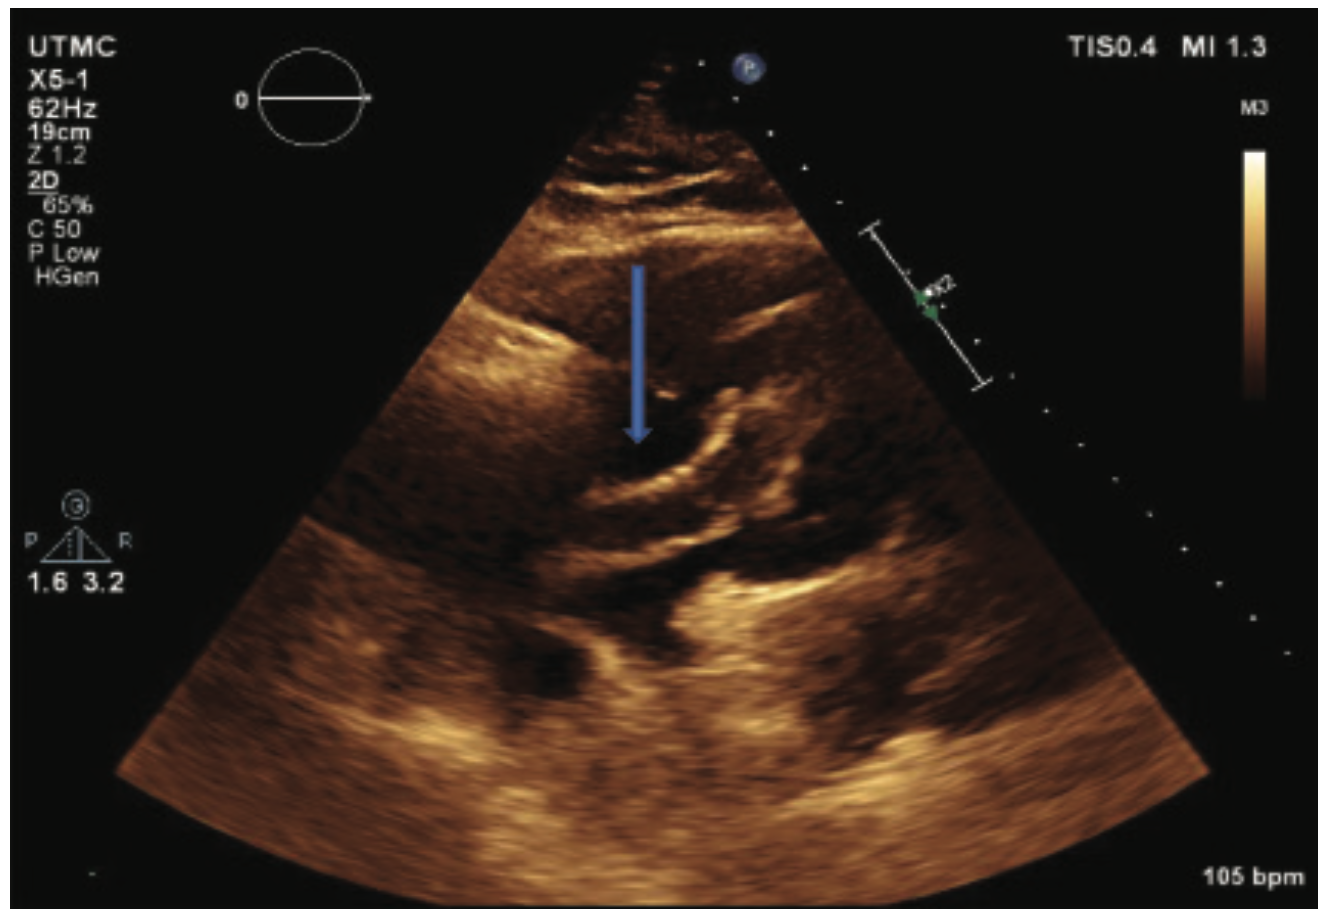

An 80-year-old male with no known past medical history presented to the emergency department at an outside facility with increasing dyspnea for the past ten days. Two weeks prior to his presentation, the patient had a fall. The patient had been immobile since then. Computed tomography (CT) angiogram of the chest showed a completely occluded right pulmonary artery and a partially occluded left pulmonary artery (Figure 1). Duplex of the lower extremity also revealed thrombosis of the left common femoral vein, femoropopliteal, and tibioperoneal veins. His BNP was also noted to be elevated at 306 pg/ml and his troponins were also elevated at 0.09 ng/ml (upper limit was 0.04 ng/ml). As he was hemodynamically stable, the patient was transferred to our facility for possible catheter-directed thrombolysis given his clinical picture of submassive pulmonary embolism. On arrival, an emergent bedside echocardiogram showed a clot in transit from the right atrium to the right ventricle (Figure 2), as well as a severely enlarged right ventricle and moderate tricuspid regurgitation. Due to the huge clot burden, right ventricular strain, and clot in transit, the patient underwent emergent surgical embolectomy. Surgery was successful in removing most of the clot with no complications. Intraoperatively, the clot was found to extend from the right atrium through the tricuspid valve into the right ventricle and all the way to the main pulmonary arteries. There was some residual thrombus in subsegmental areas that was left for medical treatment. The patient had remarkable improvement and was able to go home in a couple of days. He was discharged on rivaroxaban. On follow-up, the patient elected to have an inferior vena cava (IVC) filter placed, which was done successfully. Repeat CT angiography was done 4 months after presentation and showed resolution of the remaining thrombi. The patient continues to do clinically well on outpatient follow-up.

Echocardiography remains the gold standard for risk stratification of pulmonary embolism as well as for making the diagnosis of intracardiac thrombi, with the added benefit of obtaining an idea of the clot origin. Morphologically, the right heart clots can be divided into two types, A and B. Type A clots have a worm-like shape, are very mobile, and usually represent peripheral venous clots that lodge temporarily into the right heart. Type B, on the other hand, are similar in shape to the left heart thrombi, less mobile, attach to the right atrial or ventricular wall, and have broad-based attachment, indicating that Type B clots develop within the right heart.7